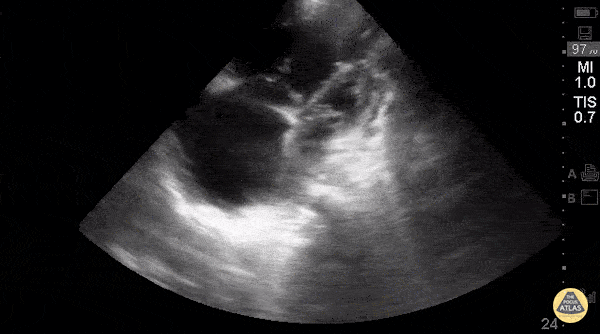

Right Ventricular Dysfunction - Right-Sided Heart Failure (A4C)

Young woman with a history of Idiopathic Pulmonary Arterial Hypertension w/ resultant R heart failure who came in short of breath. Greg Powell, MD